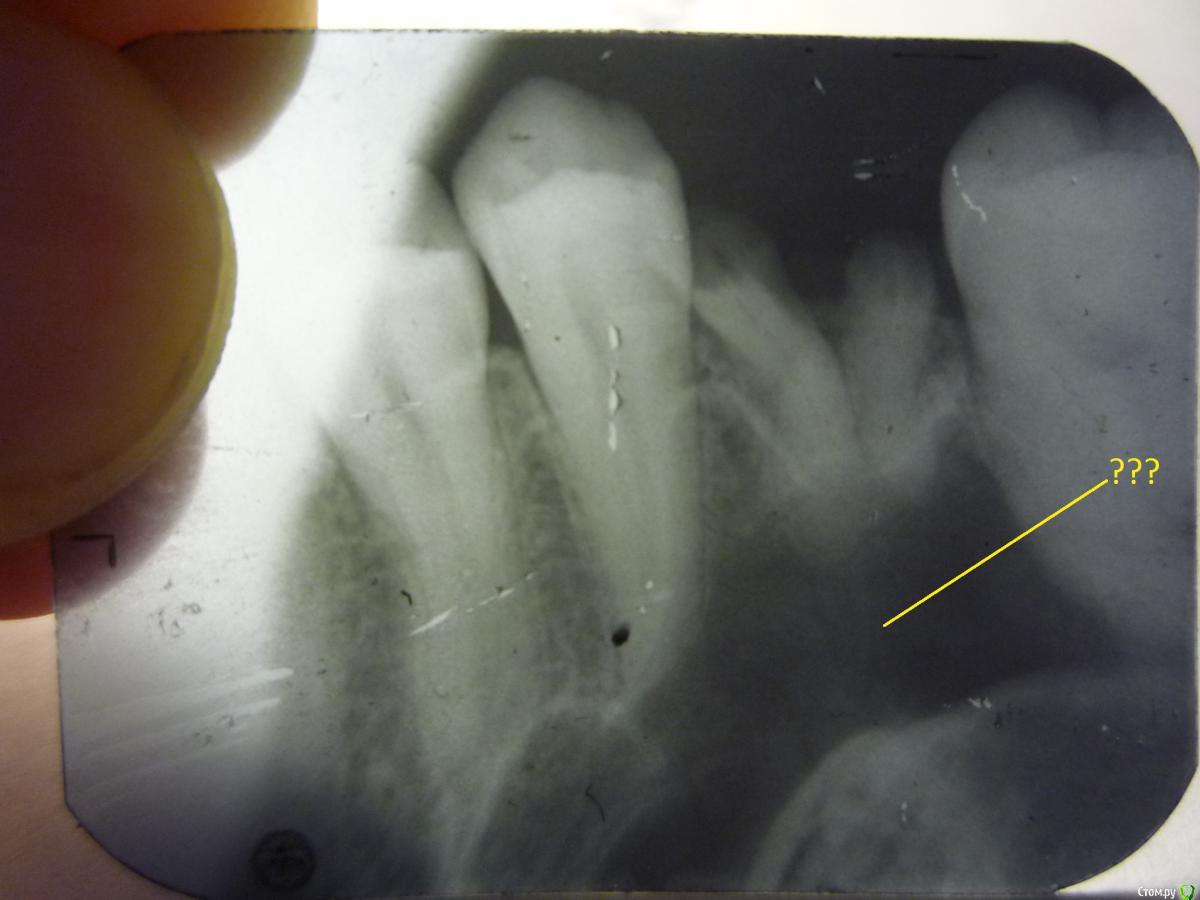

В детстве зуб 26 прогнил и был сломан под корень при попытке удаления. В течение лет ~15 оставался в десне. От зуба осталось 3 выглядывающих корешка с черными пеньками. Интересует темная область на снимке под корешками, что за область, представляет ли это опасность, возможна ли здесь имплантация.

Корешки уже удалены.

Верхнечелюстной синус. Удаляйте и имплантируйтесь.